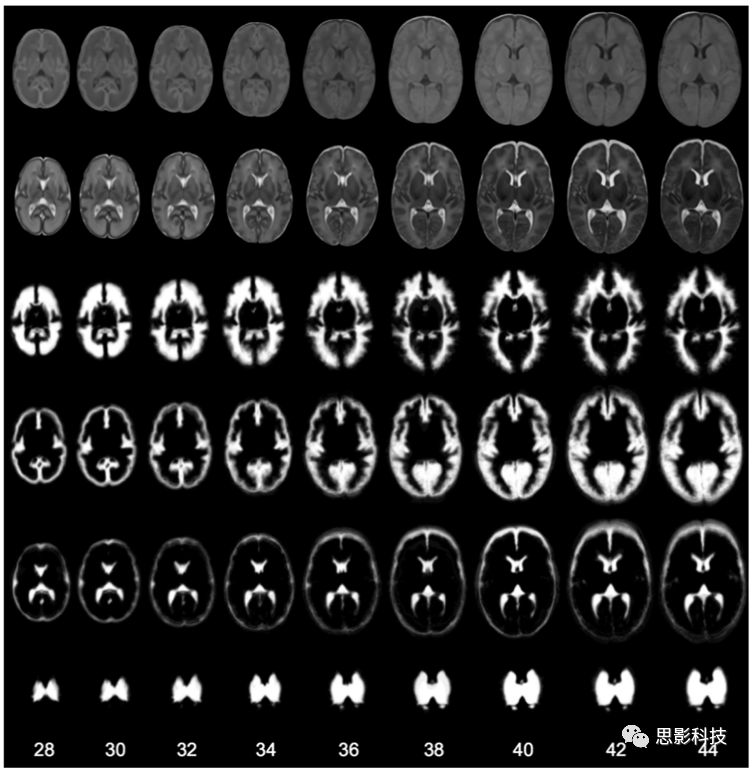

d) 由于在此期間大腦的快速發(fā)育,圍產(chǎn)期大腦的形狀和結(jié)構(gòu)外觀差異很大。皮質(zhì)帶迅速折疊并形成深的灰質(zhì)結(jié)構(gòu)。此外,WM髓鞘形成在大腦發(fā)育過程中是一個持續(xù)的過程,在不同的WM區(qū)域逐漸明顯。由于不同掃描年齡的受試者在解剖學(xué)特征上存在這些差異,因此對其進(jìn)行精確的定位具有挑戰(zhàn)性。圖4展示了在新生兒大腦中隨著掃描年齡的增加所發(fā)生的變化。

4所示。分別在PMA 28周、32周、36周和44周時獲得新生兒大腦T2 MR圖像(從左至右)。